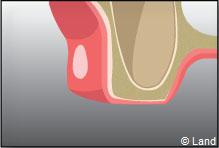

Certaines dents n’arrivent pas à faire leur éruption sur l’arcade correctement, présentent un accès difficile (dents de sagesses), ont des racines divergentes ou très courbées, ou sont considérablement abîmées (carie importante par exemple). Aussi elles restent souvent en partie ou totalement incluses dans l’os. On procède alors à une extraction chirurgicale.

L’intervention commence là aussi par une anesthésie locale, puis le chirurgien-dentiste procède à une incision de la gencive et à un dégagement du tissu osseux autour de la dent.

Parfois cette dernière est sectionnée pour ne pas traumatiser l’os souvent responsable de suites opératoires douloureuses.

Une fois la dent enlevée, la cavité est nettoyée. En cas d’une dent souffrant d’inflammation, le tissu infecté sera également enlevé.